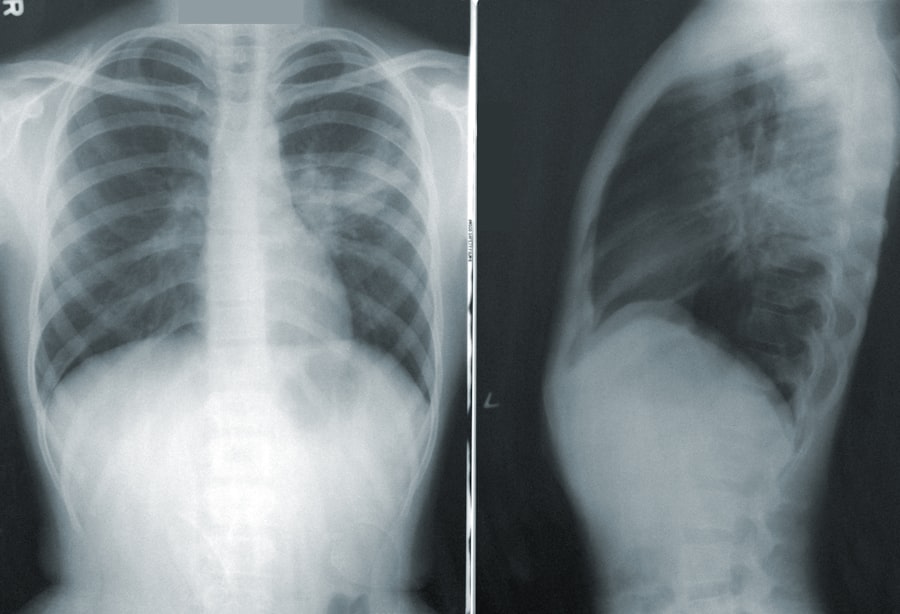

A diagnózis megerősítésére különböző képalkotó eljárásokat alkalmaznak. Az ultrahangos vizsgálat például lehetővé teszi az erek állapotának valós idejű megfigyelését, míg a CT- vagy MRI-vizsgálatok részletesebb képet adhatnak az érintett területekről. Ezen kívül angiográfiát is végezhetnek, amely során kontrasztanyagot juttatnak az érbe, hogy kiemeljék a szűkületeket és plakkokat.

Az érszűkület diagnosztizálása során az orvosok különböző teszteket végeznek annak érdekében, hogy pontosan meghatározzák a betegség mértékét és típusát. A leggyakoribb módszer a Doppler-ultrahang, amely lehetővé teszi az artériák véráramlásának mérését. Ezzel a módszerrel az orvosok képesek észlelni a szűkületeket és azok súlyosságát.